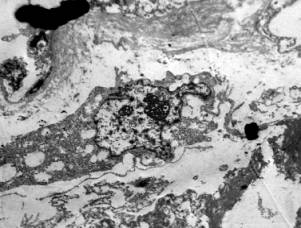

Патоморфологические изменения при гриппе и сепсисе в первые пять суток развития СОЛП характеризуются диффузным альвеолярным повреждением с усилением микропиноцитозного транспорта эндотелия, отеком интерстиция и резким субэпителиальным отеком. При сепсисе помимо указанных проявлений наблюдаются начальные явления фиброза аэрогематического барьера, что объясняется предшествующей, достаточно длительной для создания условий синтеза протеинов внеклеточного матрикса, системной воспалительной реакцией. Пролиферация и гиперплазия клеток альвеолярного эпителия гораздо раньше, чаще и с большей интенсивностью выявляется в случаях вирус-индуцированного заболевания. Этот факт объясняется тем, что при сепсисе, в отличие от вирусного, повреждение альвеолярного эпителия возникает вторично как следствие изменений интерстиция и базальной мембраны, а поэтому проявляется позже от начала регистрации клинических критериев СОЛП. Интерстициальный отек, и последующий интерстициальный фиброз по данным электронной микроскопии, более выражены при сепсисе, чем при гриппе, а признаки начинающейся карнификации имеют обратную взаимозависимость (Рис. 1, 2, 3, 4.).

Рис. 3. Электронная микро­фотография. Грипп 15 суток. Расширение интерстиция за счет отека и отложения протеинов внеклеточного матрикса (стрелки). Организация волокон коллагена в пучки, между которыми видны широкие прослойки плотного межфибриллярного вещества (обведено пунктиром). Ув. 20000.